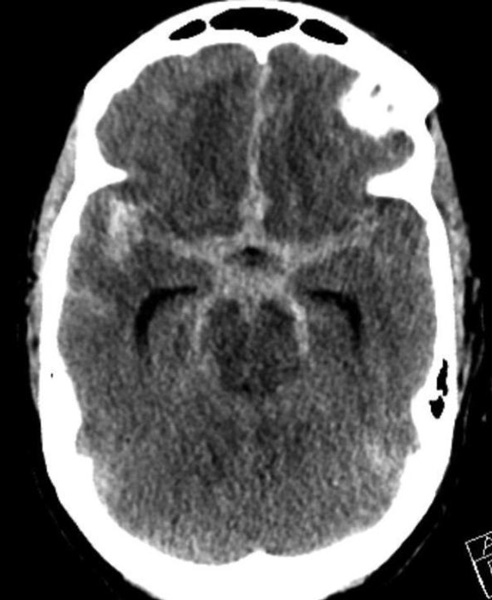

The Pattern of Hemorrhage was diffuse and generalized. On more careful analysis, however, there appeared to be focal hemorrhagic clot within the anterior inter-hemispheric fissure which raised greater suspicion for the Anterior Communicating Aneurysm as the source of hemorrhage. Although Acom Aneurysm was smaller, it’s irregular shape and eccentric “nipple” suggested potential rupture point. (Figure 3.)